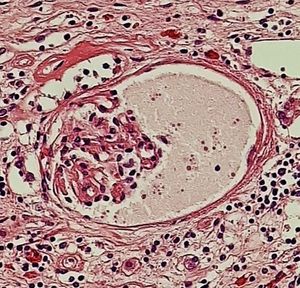

사구체주머니는 신장의 사구체를 둘러싸는 구조로, 혈액 여과를 담당한다. 사구체주머니는 혈관극과 요세관극 두 개의 극을 가지며, 벽측 층, 보우만 공간, 내장 층, 여과 장벽으로 구성된다. 벽측 층은 여과 기능을 하지 않으며, 보우만 공간은 여과액이 모이는 공간이다. 내장 층은 발돌기 세포로 구성되어 있으며, 여과 장벽은 혈액 내 물질의 통과를 조절한다. 사구체주머니는 사구체 여과율 측정에 중요한 역할을 하며, 신부전과 같은 질환과 관련될 수 있다. 이 구조는 윌리엄 보우만의 이름을 따서 명명되었지만, 알렉산드르 슘랸스키가 먼저 기술했다.

사구체주머니(보우만주머니)는 신장의 신소체를 구성하는 중요한 부분으로, 사구체를 감싸고 있는 주머니 모양의 구조물이다. 사구체주머니의 구조는 크게 외부의 극과 내부의 층으로 나눌 수 있다.

- '''보우만 공간''' (또는 "요 공간", "캡슐 공간"): 벽측 층과 아래 설명할 내장 층 사이에 있는 공간으로, 사구체에서 여과된 액체(여과액)가 모이는 곳이다.[1]

- '''내장 층''': 사구체 모세혈관을 직접 둘러싸고 있는 층으로, 특수화된 세포인 발돌기 세포(족세포)로 구성된다.

내장 층과 사구체 모세혈관 사이에는 혈액을 여과하는 여과 장벽이 존재한다. 이 장벽은 혈액 속 특정 성분만 선택적으로 통과시켜 여과액을 만드는 역할을 한다.

두꺼운 사구체 기저막 바로 아래에 있으며, 발돌기 세포(족세포)로 구성되어 있다. 장측 엽 바로 아래에는 사구체가 있다.2. 3. 보먼강 (요강)

보먼강(Bowman's space)은 '요강' 또는 '캡슐 공간'이라고도 한다. 이 공간은 사구체주머니의 벽측 층(벽측 엽)과 내장 층(장측 엽) 사이에 위치한다.[1][6] 사구체에서 여과된 액체(여과액)는 발세포(족세포) 사이의 여과 슬릿[6]을 통과하여 보먼강으로 들어온다.[1]2. 4. 혈관극과 요세관극

여과 장벽은 사구체 모세혈관의 창상 내피, 내피 세포와 발돌기 세포(족세포)의 융합된 기저판, 그리고 발돌기 세포의 여과 틈새(여과 슬릿)[6]로 구성된다. 이 장벽은 물, 이온, 그리고 작은 분자들이 혈류에서 보우만 공간으로 통과하도록 허용하는 역할을 한다. 반면, 알부민과 같이 크거나 음전하를 띤 단백질의 통과는 막는다.[1]여과 장벽의 기저판은 세 개의 층으로 이루어져 있다. 가장 바깥쪽 층은 발돌기 세포 돌기 옆에 위치한 lamina rara externa|라미나 라라 엑스테르나lat이다. 안쪽 층은 내피 세포 옆에 있는 lamina rara interna|라미나 라라 인테르나lat이다. 마지막으로 중앙에는 어두운 영역인 lamina densa|라미나 덴사lat가 있다. 이 층은 제4형 콜라겐과 라미닌으로 이루어진 그물망 구조를 가지며, 선택적으로 거대 분자를 걸러내는 필터 역할을 수행한다.